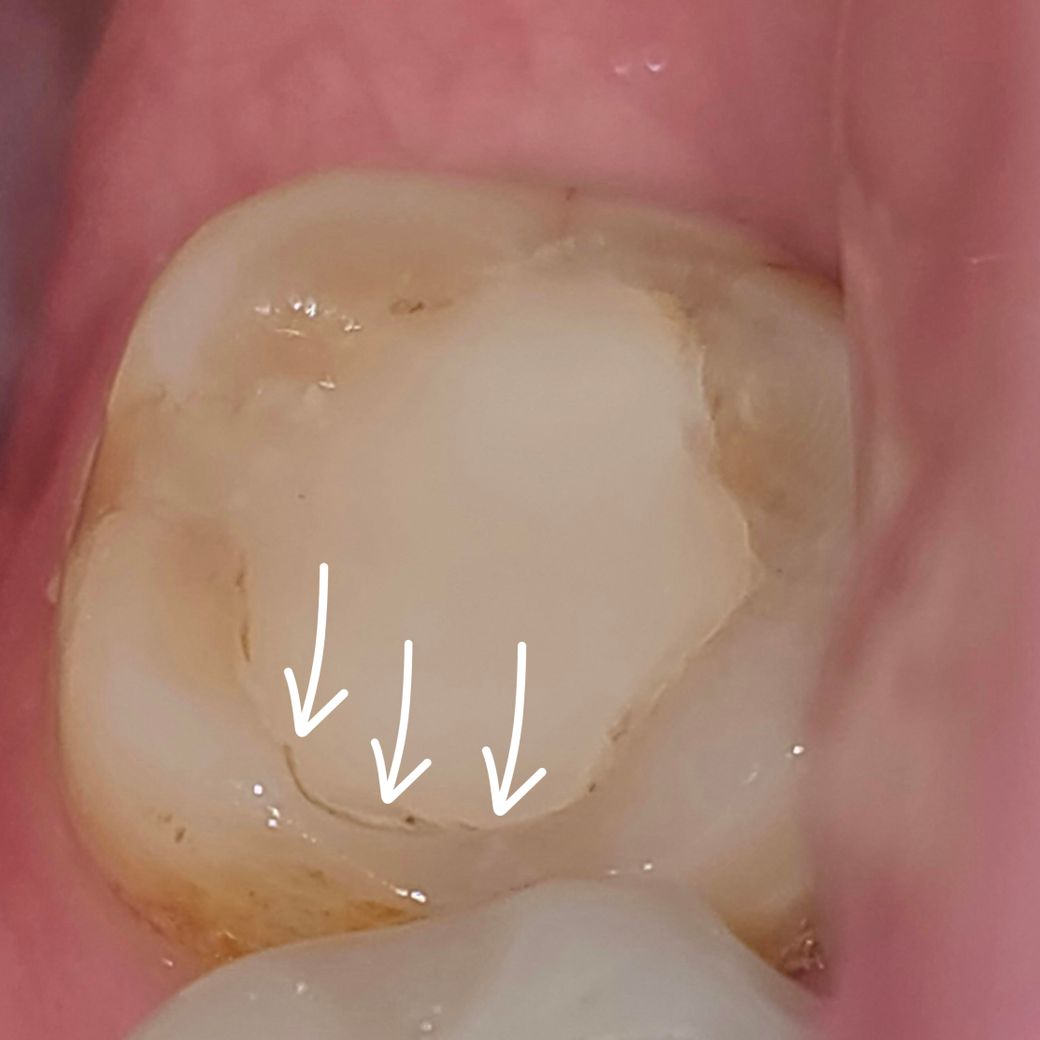

치과 필링 치료 후 플라스틱 이쑤시개로 긁음.

사진은 제 치아와 사용한 이쑤시개 입니다.

하루 정도 지난 뒤 치아와 필링 경계면에 착색? 같은게 있어서 긁어 낼 겸 + 빠작하는 소리를 들어서 혹시 틈이 생긴건 아닌지 걱정되어

필링과 치아의 경계부분을 전체적으로 플라스틱 이쑤시개로 긁으며 틈 또는 단차가 있는지 확인했는데..괜찮을까요?

혹시 제가 긁어서 표면이 파이거나 틈이 생기거나 하진 않을까요? 긁다보니 뭔가 제 치아보다 무르고 부드러운 느낌이라 확인겸 더 세게 긁은 것 같아요.

레진 재료로 보입니다.

치료 후 12시간 뒤 아주 작게 빠작 하는 소리가 들렸는데 뭔가요? 레진필링이나 다른 재료가 경화가 과정에서 수축이 발생하는 경우 소리가 날수 있습니다.

필링이라고만 들었는데 재료가 뭔가요? 레진일 가능성이 높으며, 보다 정확하게는 치료받은 치과에 문의를 권합니다.

확인을 하는 것은 문제가 되지 않으나, 과도한 힘을 주지 않는 것이 좋으며, 만약 단차가 있는 경우 그부분에 세균이 침투해 충치가 재발할수 있습니다.

쎄게 긁는 경우 틈이 생길수 있으며, 불안한 경우 치과에 방문하여 저검을 받아보길 권합니다.